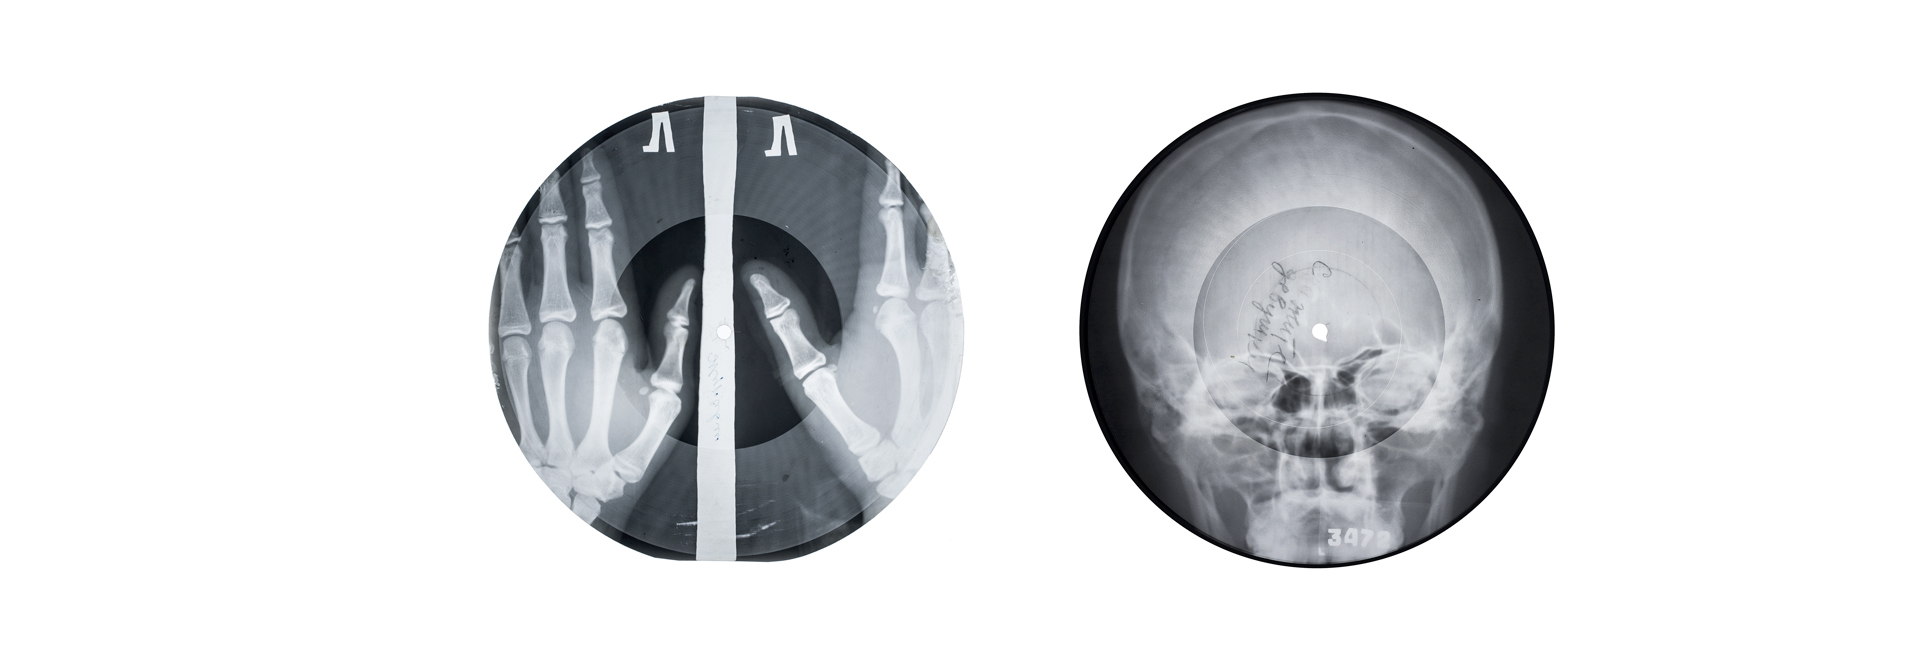

Причины и лечение появления пластинок на костях